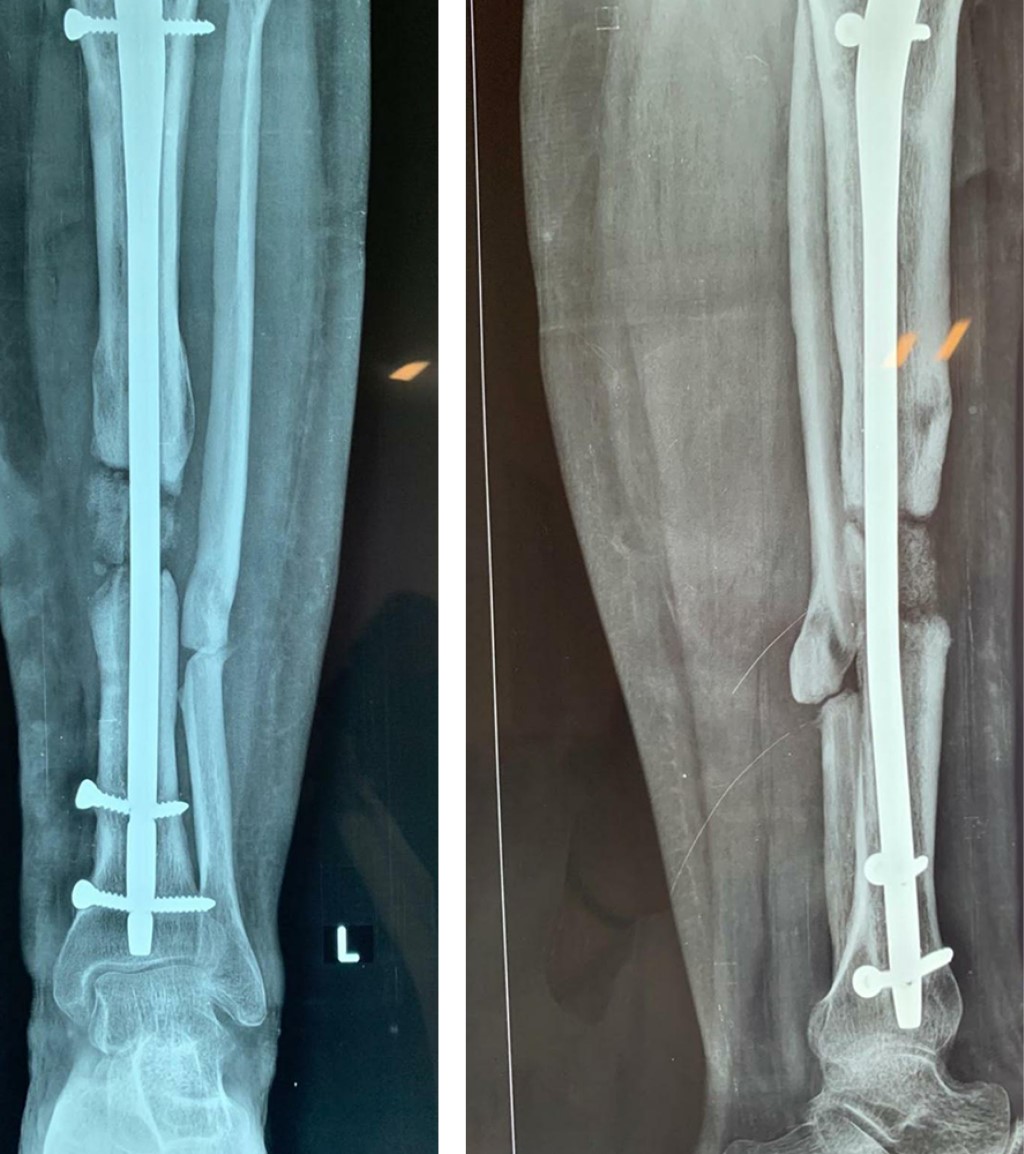

Después de nueve meses se observa no unión de espectro atrófico en tibia y peroné izquierdos (Figura 1) por lo que se decide su internamiento para realización de técnica de Masquelet, se informa a la paciente acerca del pronóstico y posibles múltiples procedimientos.

Figura 1